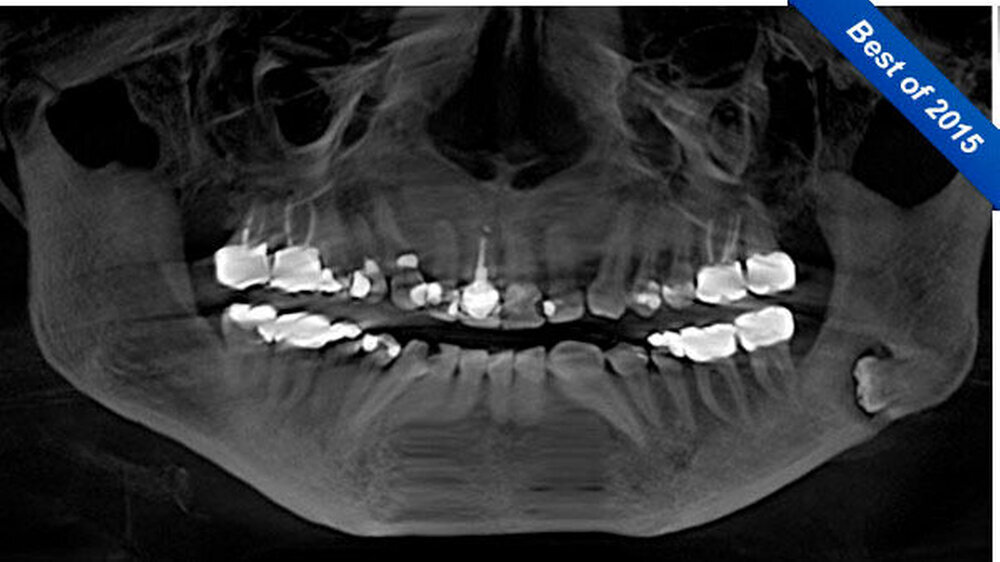

Die 53-Jährige stellte sich mit klinischem Verdacht auf einen dentogenen Abszess im Unterkiefer linksseitig bei ihrem Hauszahnarzt vor. Bei durchgeführtem OPT zeigte sich ein tief retinierter und impaktierter Zahn 38, welcher sich röntgenologisch parallel zum Unterkieferrand abbildete. Weiterhin imponierte dort eine apikale Transluzenz, die diesen Weisheitszahn bei ansonsten gut saniertem Gebiss als Infektfokus erscheinen ließ.

Es erfolgte durch den Hauszahnarzt zunächst eine intraorale Inzision von vestibulär sowie der Beginn einer oralen Antibiotikatherapie mittels Clindamycin 300 mg 1-1-1. Unter regredienter Symptomatik wurde die Patientin zur weiteren Therapie überwiesen. Nach ausführlicher Anamnese und klinischer Untersuchung wurde die Röntgendiagnostik durch eine Digitale Volumentomografie (DVT) zwecks exakter Lagebestimmung des retinierten Zahns 38 erweitert. Das DVT war insbesondere im Hinblick auf die anatomische Lagebeziehung zum Nervus alveolaris inferior aber auch zur Evaluation der Osteodestruktion nach stattgehabtem Entzündungsgeschehen indiziert.

Hierbei kam der Zahn 38 in seiner Längsachse rund 6 mm parallel zum Unterrand der Mandibula im Bereich des linken Kieferwinkels zur Darstellung. Weiterhin fiel eine perikoronare Transluzenz und die enge räumliche Lagebeziehung zum N. alveolaris inferior auf. Im weiteren Verlauf wurde die Indikation zur operativen Entfernung des Zahns von extraoral gestellt. Die Indikation zu diesem Eingriff war in der Sanierung des Infektionsherdes und damit der Prävention einer erneuten Entzündung und weiterer osteolytischen Schädigung des Unterkiefers begründet.